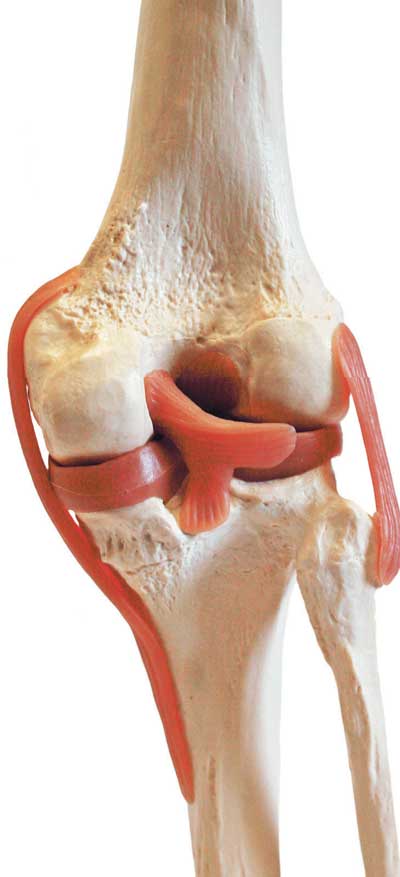

Сустав – самая распространенная и сложная форма соединения костей. Обязательными элементами любого сустава, независимо от места расположения и степени подвижности, являются суставные поверхности, суставная сумка и суставная полость.

Соединение костей в коленном суставе (вверху – рентген, внизу – модель)

Суставные поверхности костей, образующие сустав, плотно прилегают друг к другу. Они покрыты особым гиалиновым хрящом, чья гладкая поверхность и эластичность облегчают движение в суставе, смягчают испытываемые им толчки и сотрясения.

Суставные поверхности костей окружает суставная капсула – оболочка из соединительной ткани. Обычно она крепится к костям в месте перехода суставной поверхности в надкостницу и прочно с ней срастается. Снаружи капсула укреплена связками, которые располагаются в местах наибольшей нагрузки.

Суставные поверхности и капсула ограничивают собой небольшое герметично закрытое пространство – полость сустава, заполненную малым количеством вязкой синовиальной жидкости, роль которой заключается в уменьшении трения в суставах при движении. Благодаря отрицательному давлению в суставной полости поверхности костей тесно прилегают друг к другу.